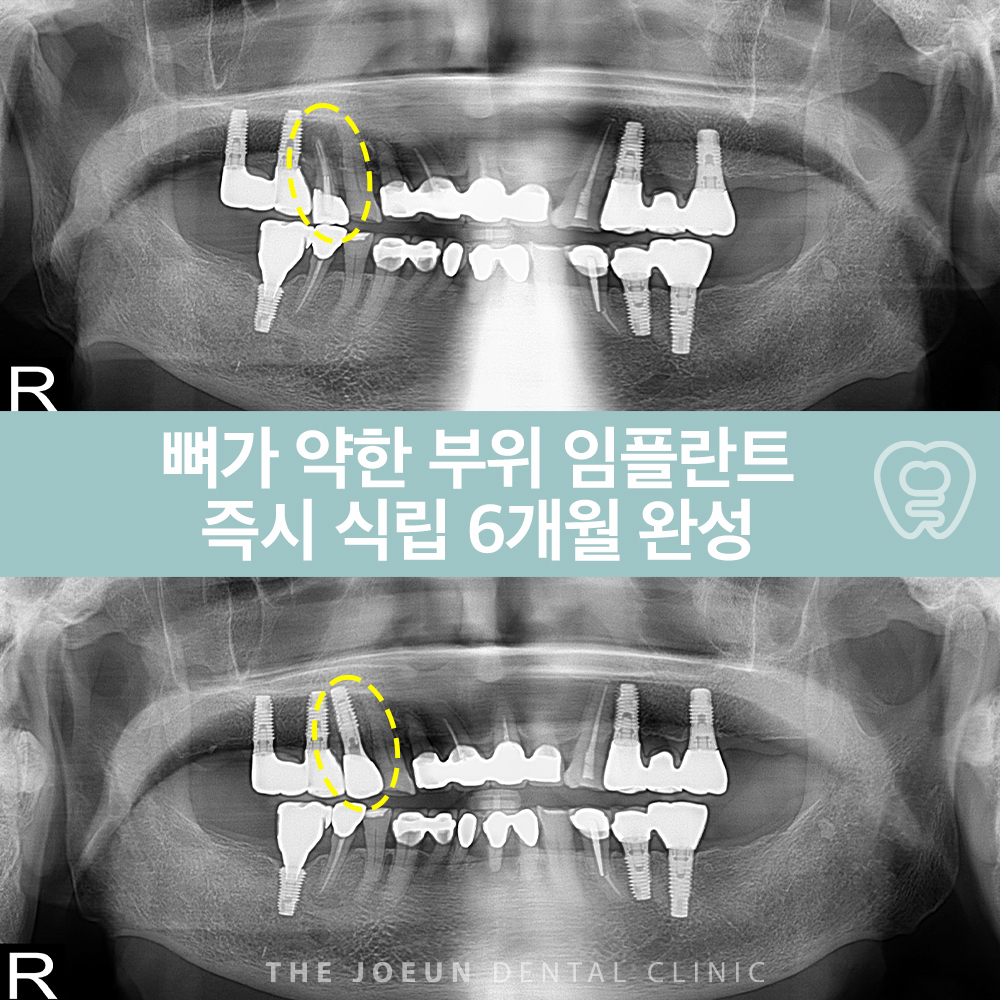

계명대치과 뼈가 약한 부위 임플란트 즉시 식립 6개월 완성

2025-11-14

계명대치과 뼈가 약한 부위 임플란트 즉시 식립 6개월 완성 현대인에게 치과 치료는 단순한 의학적 행위…